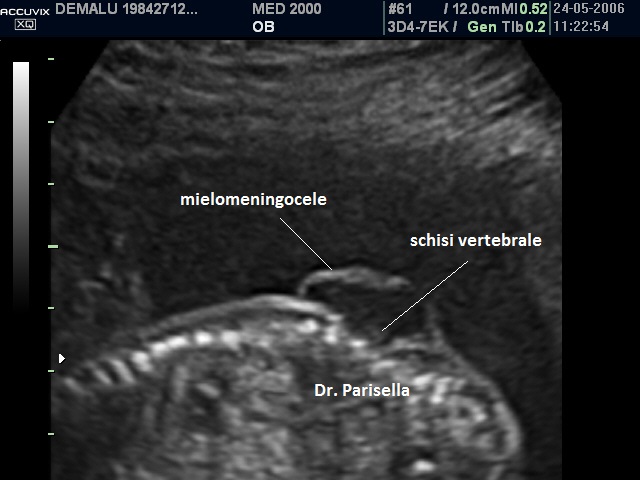

La spina bifida aperta è caratterizzata da un difetto osseo posteriore delle vertebre, interessamento a tutto spessore della cute e protrusione del contenuto spinale attraverso il difetto osseo. Il contenuto spinale può essere rappresentato da una tasca contenente le sole meningi (meningocele) o da una tasca contenente meningi e tessuto nervoso (mielomeningocele); più frequentemente il difetto spinale si localizza a livello del tratto lombo-sacrale della colonna vertebrale.

Nelle forme aperte la diagnosi ecografica prenatale si basa sui seguenti segni indiretti (1,2,3) e diretti(4,5):

4) schisi vertebrale;

5) mielomeningocele: formazione cistica settata sovrapposta alla schisi vertebrale.